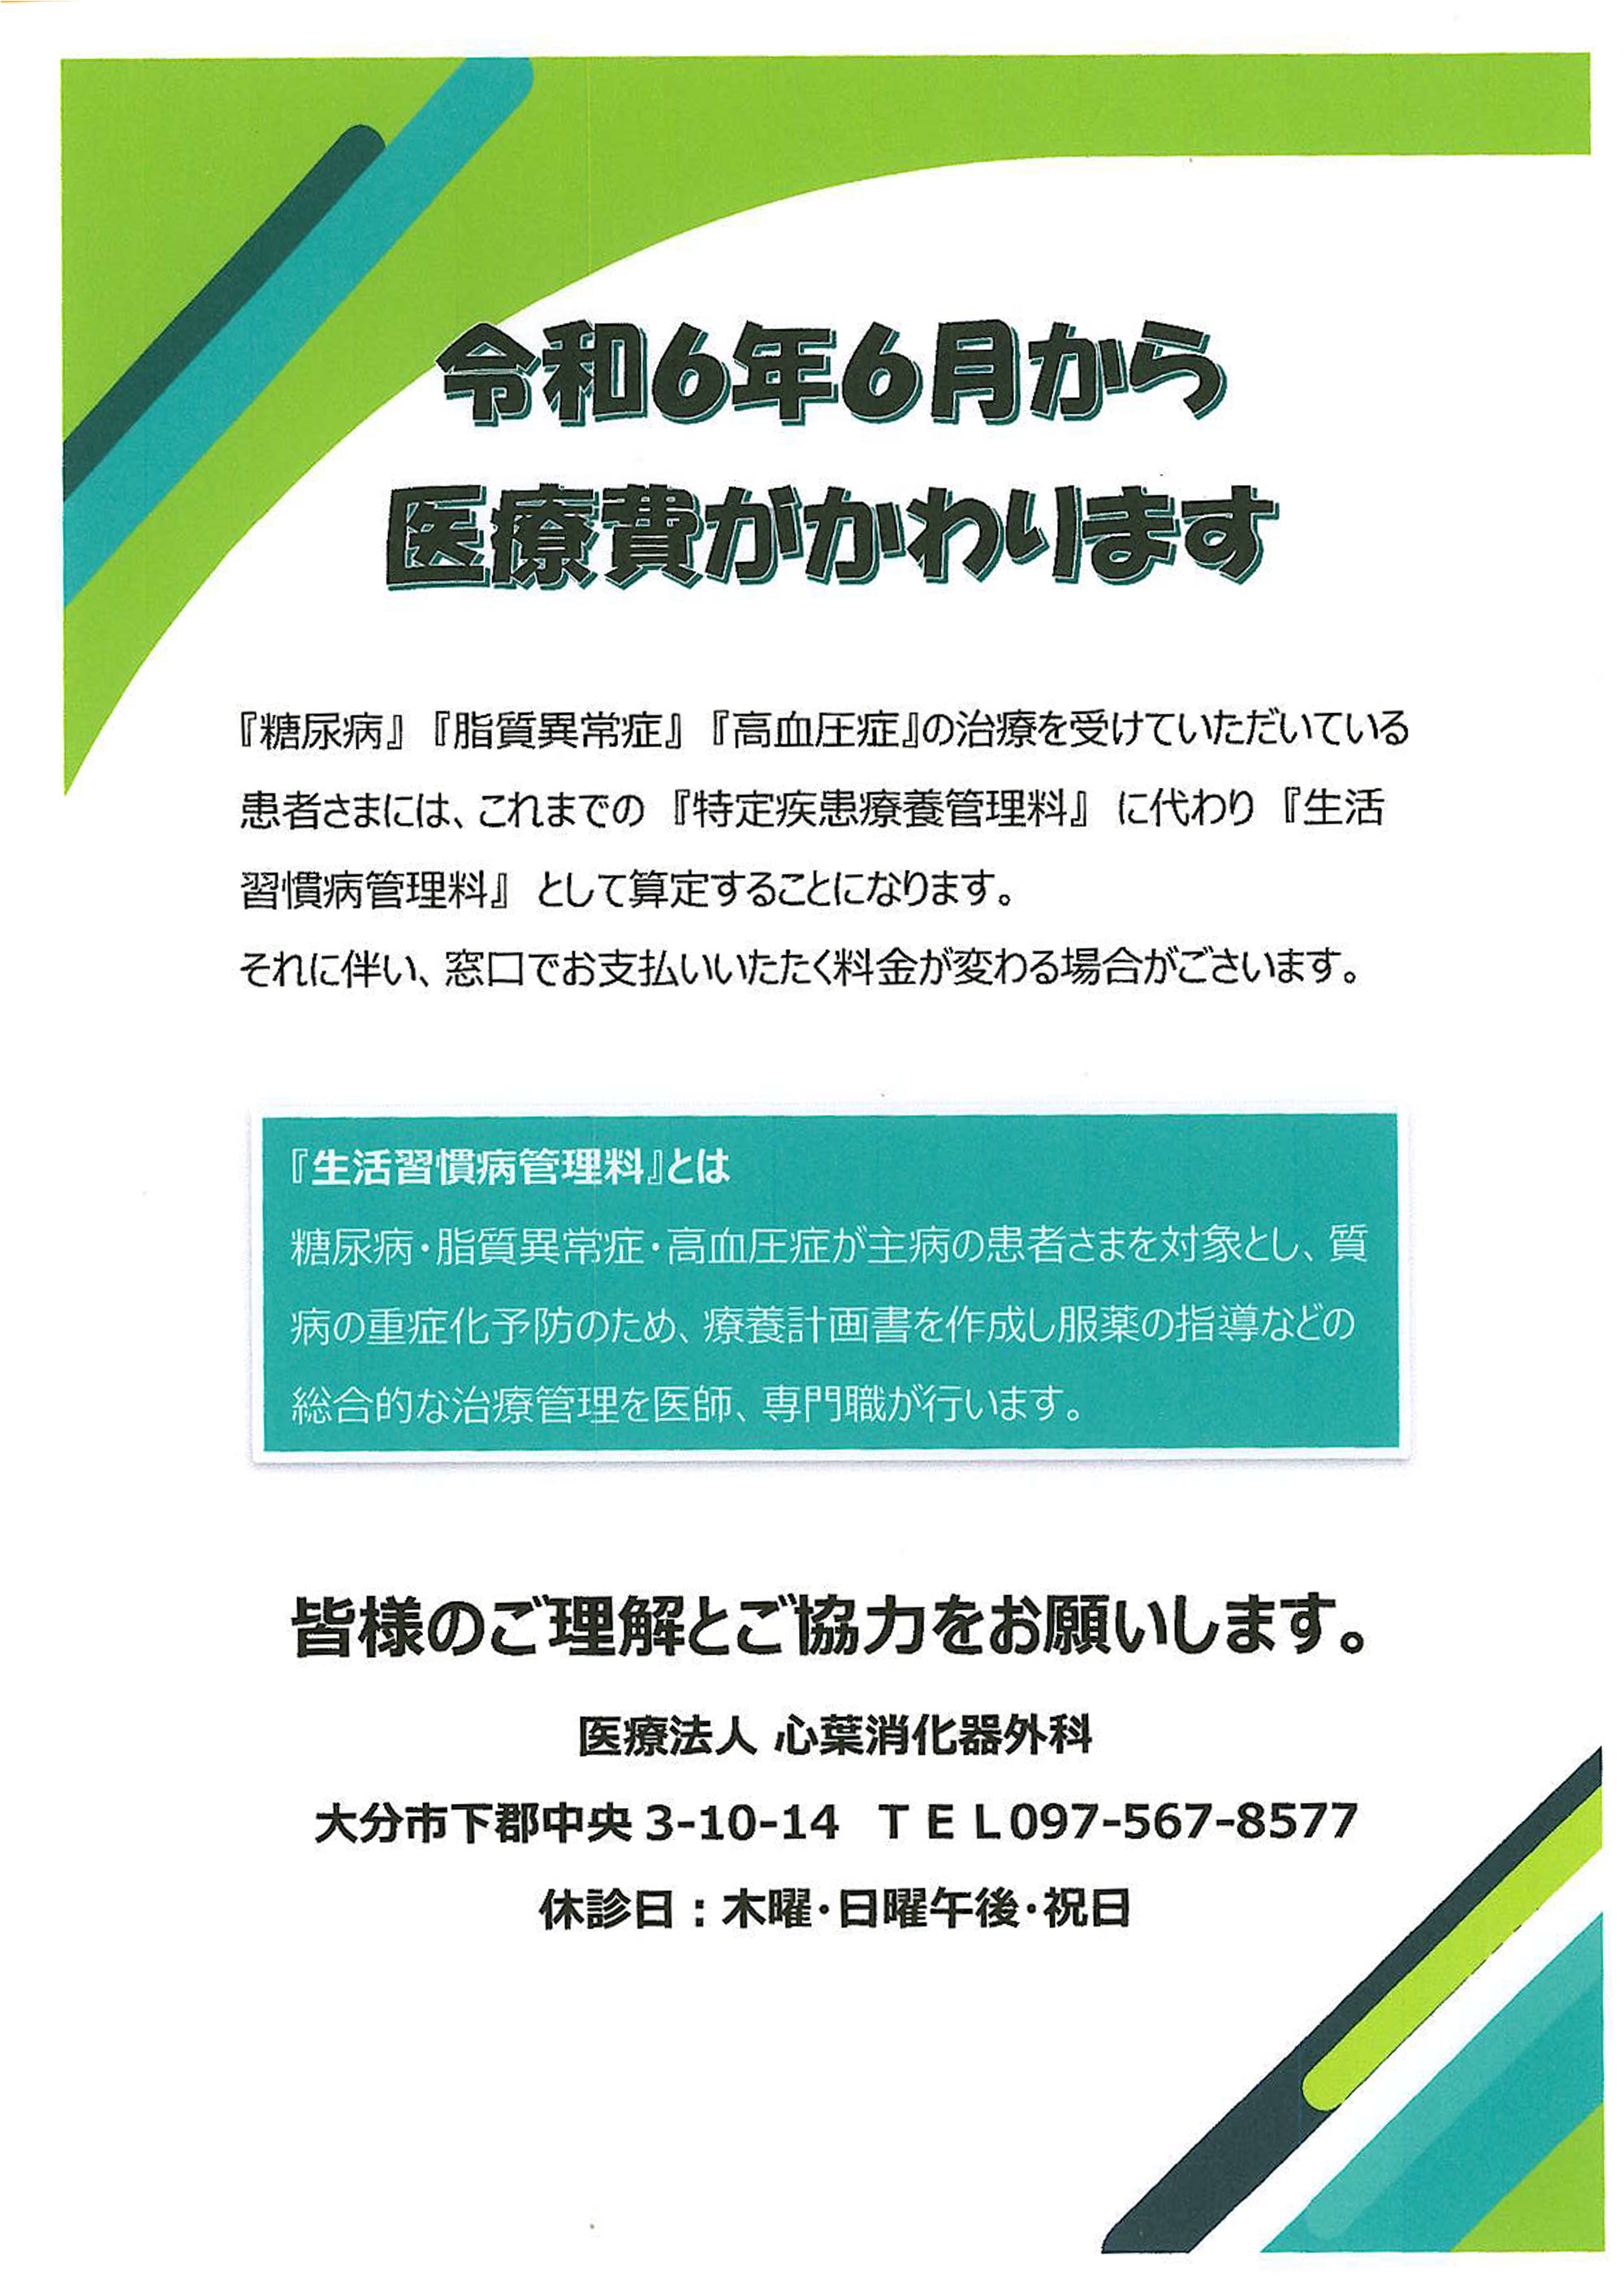

MRエラストグラフィを導入しました<メディカルスキャニング千葉, 医療法人 心葉消化器外科|トップページ,

医療法人 心葉消化器外科|トップページ, 進行性線維化を伴うCTD-ILD診療における急性増悪予防の重要性,